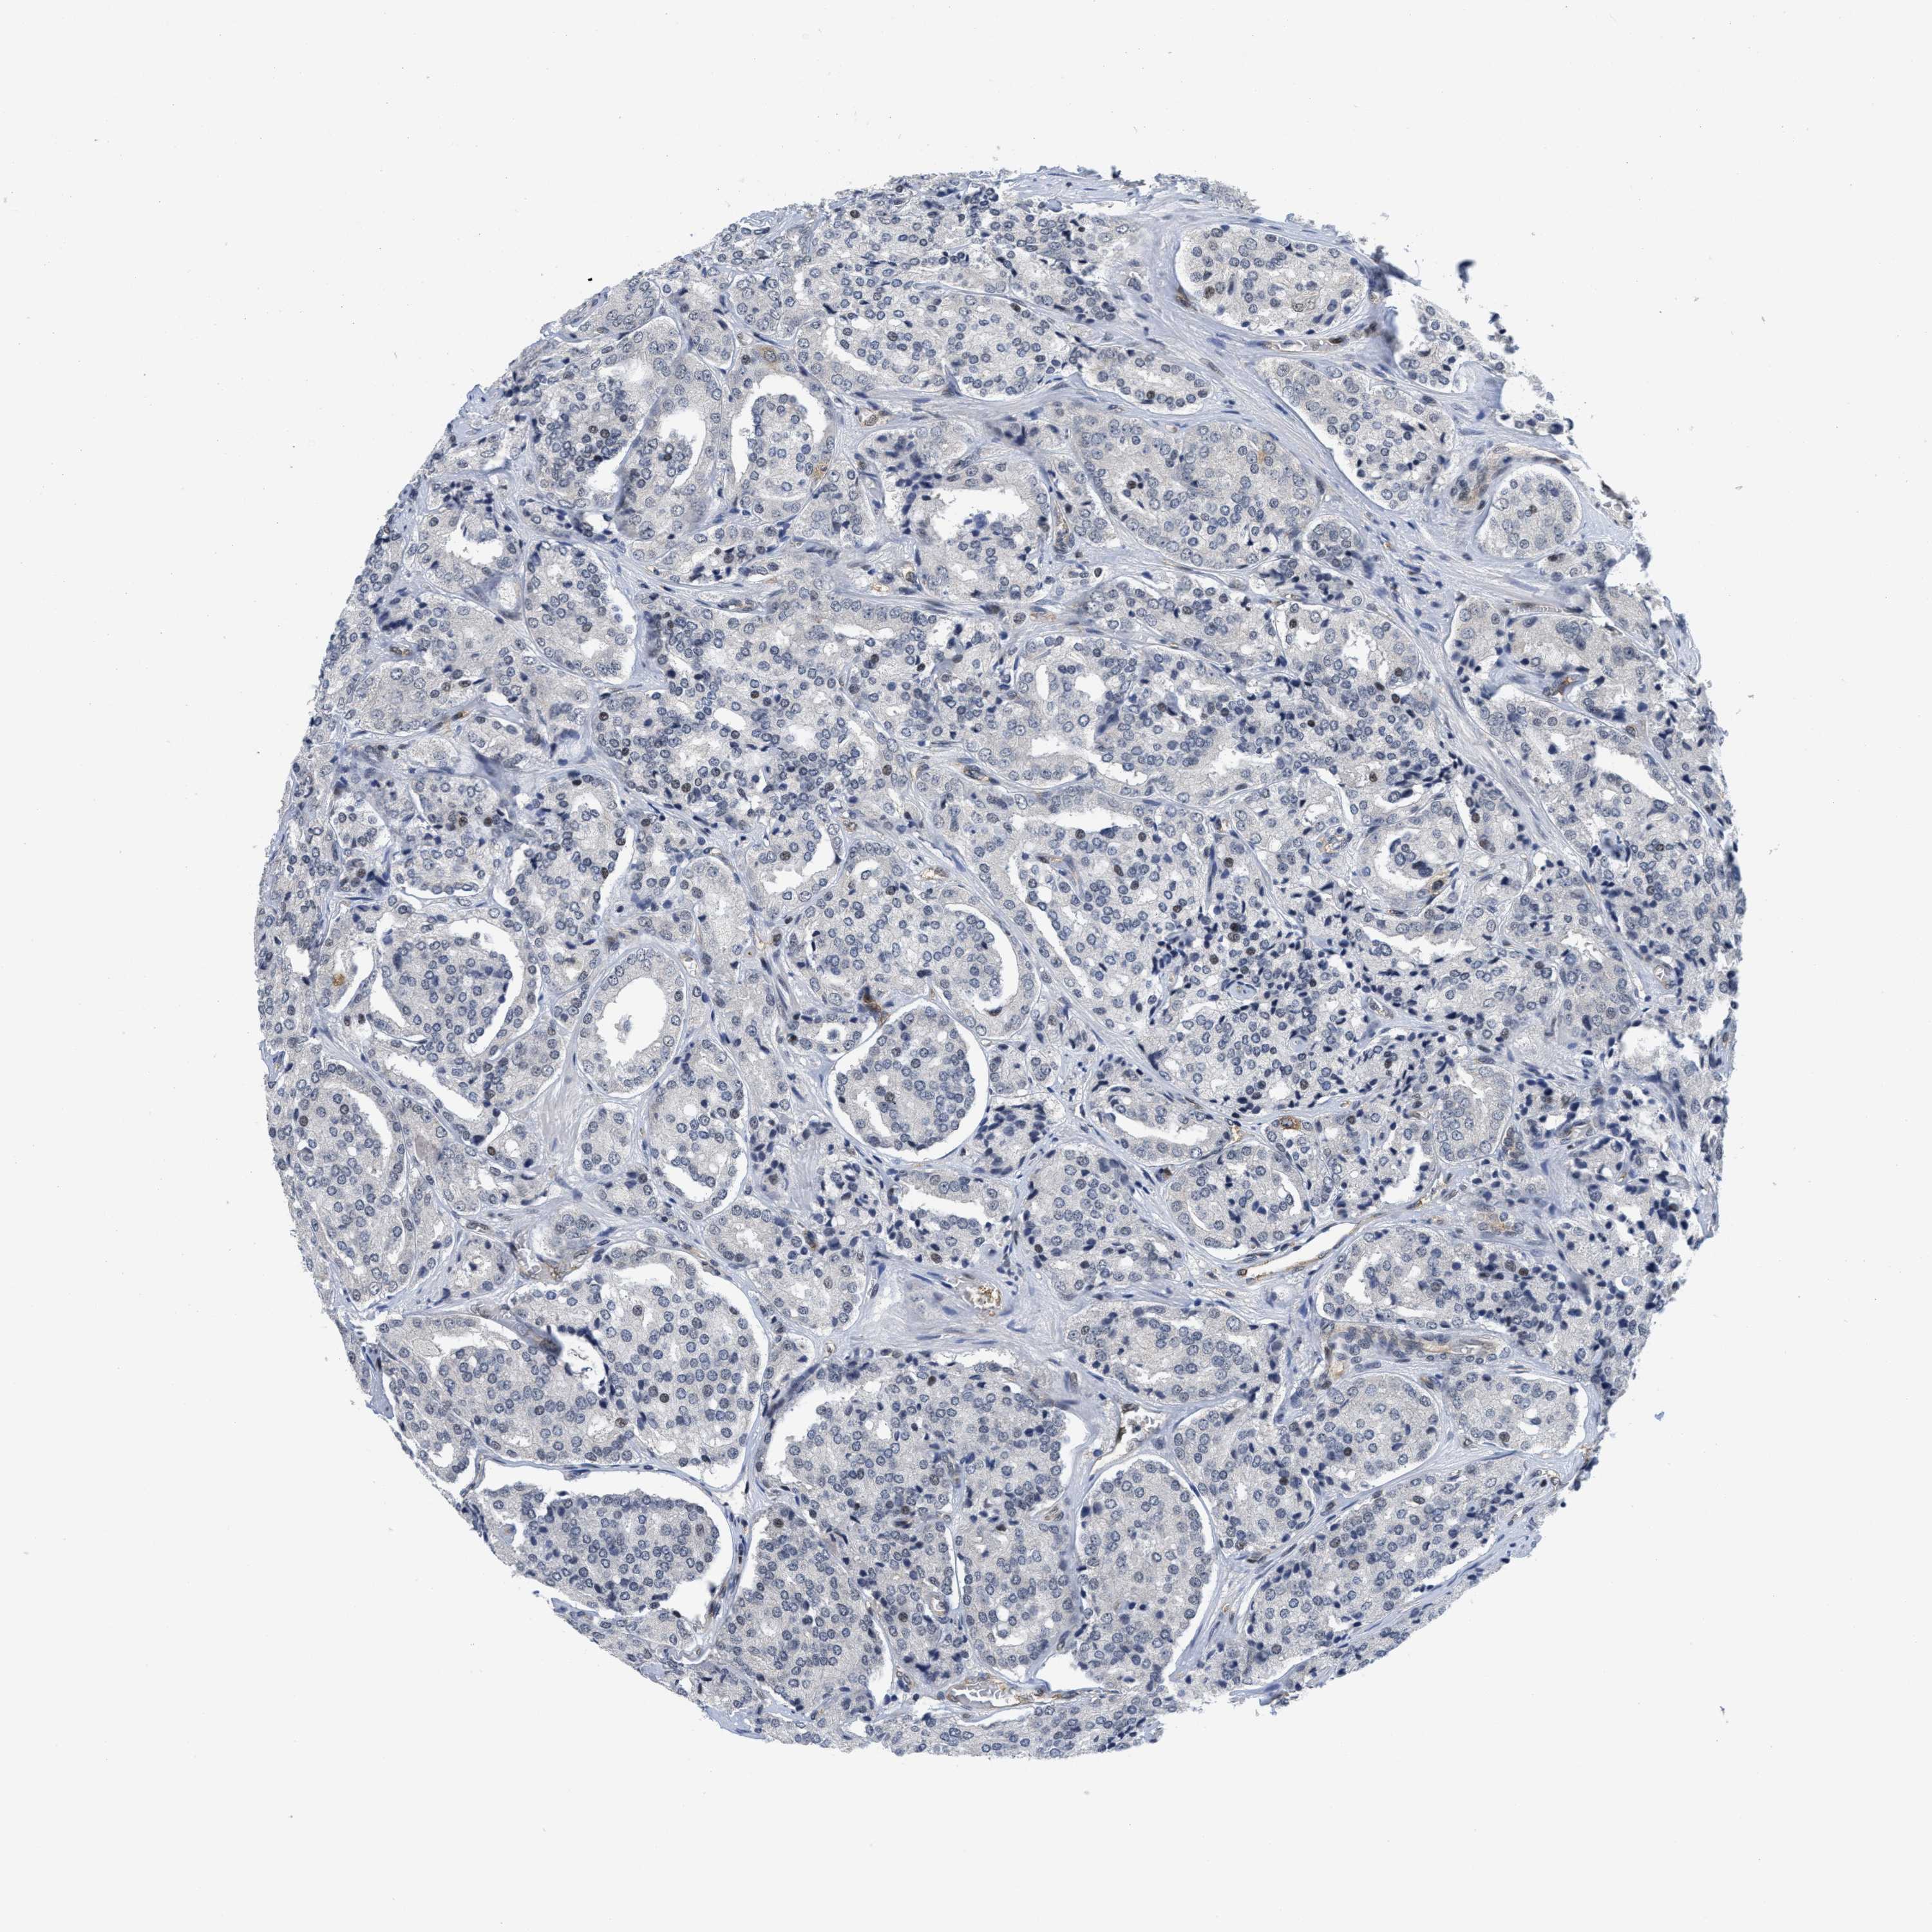

PROSTATE CANCER - Protein expressioni

A mouse-over function shows sample information and annotation data. Click on an image to view it in a full screen mode. Samples can be filtered based on level of antibody staining by selecting one or several of the following categories: high, medium, low and not detected. The assay and annotation is described here.

Note that samples used for immunohistochemistry by the Human Protein Atlas do not correspond to samples in the TCGA dataset.

Antibody stainingi

Antibody staining in the annotated cell types in the current human tissue is reported as not detected, low, medium, or high, based on conventional immunohistochemistry profiling in selected tissues. This score is based on the combination of the staining intensity and fraction of stained cells.

Each image is clickable and will lead to virtual microscopy that enables deeper exploration of all samples and also displays staining intensity scores, fraction scores and subcellular localization as well as patient and tissue information for each sample.

Antibody HPA001275

Antibody CAB017442

Staining

High

Medium

Low

Not detected

Intensity

Strong

Moderate

Weak

Negative

Quantity

>75%

75%-25%

<25%

None

Location

Nuclear

Cytoplasmic/membranous

Cytoplasmic/membranous,nuclear

Adenocarcinoma, Medium grade

Adenocarcinoma, Low grade

Adenocarcinoma, High grade